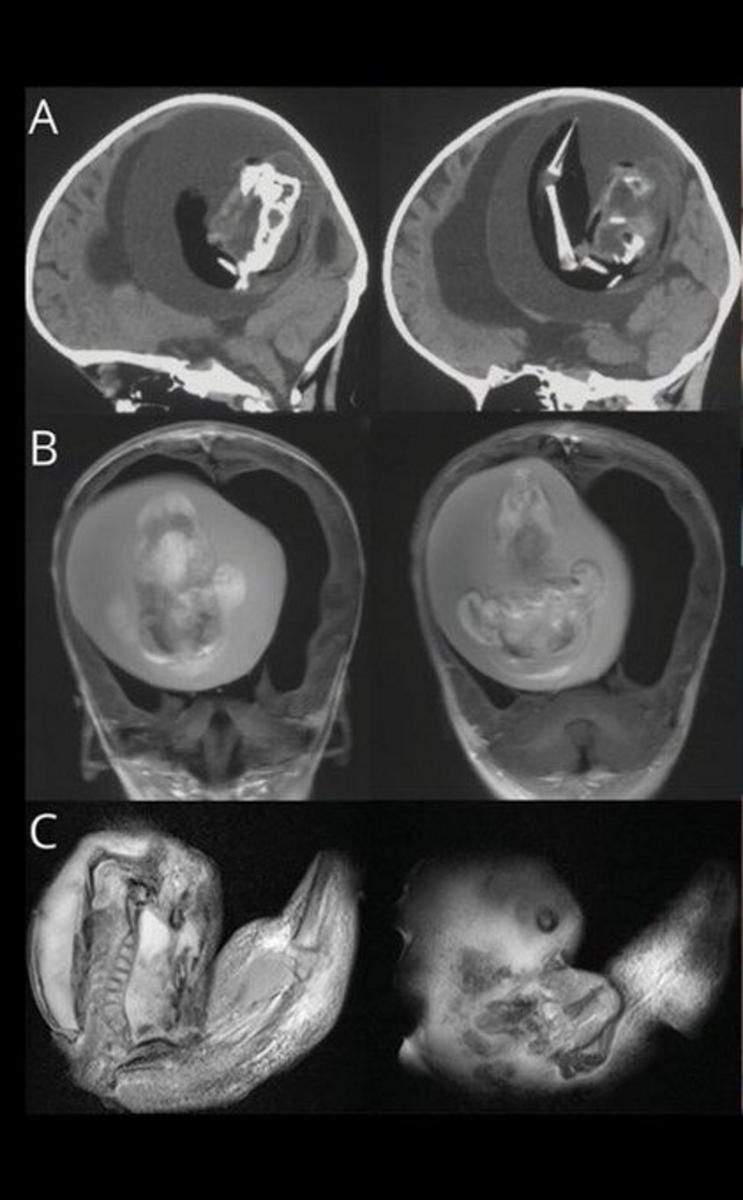

Magazyn naukowy "Neurology" opublikował opis przypadku chińskiej dziewczynki, która miała dość nietypowe objawy: powiększoną głowę oraz problemy z motoryką. Kiedy lekarze z Fudan University w Szanghaju zobaczyli wyniki tomografii komputerowej, od razu zaczęli przygotowywać się do operacji.

W czaszce dziecka znajdowała się dziwna masa, która uciskała mózg i powodowała nagromadzenie się płynu. Dopiero późniejsze badania wykazały, że był to jej… bliźniak. Płód został wchłonięty na wczesnym etapie ciąży przez silniejszego bliźniaka.

"Proszę zwrócić uwagę na ten skan. Widać wyraźnie wodogłowie, ściśnięty mózg, a także płód z kręgosłupem, kością udową i piszczelem. Masa płodowa ma kończynę górną i palce" – napisał na Twitterze Oren Gottfried, neurochirug.